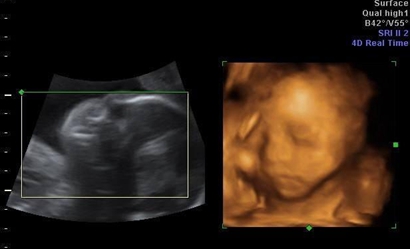

四维彩超最佳时间是在孕24周左右,5个月还未到20周做四维检查的效果并不是很好,目前网上流传的通过四维单子来看男女的方法有如下几种:

一:在彩超单上会印,顶头最右边有两行字,是英文字母和数字组成的,第一行是日期,第二行是时间,如果第一行是M开头,那就是male男,如果是F开头就是female女,第二行打头的T是时间的意思。

二:彩超单上通常有“双侧肾盂分离”,那90%是男孩;如果是“双侧肾盂未见明显分离”,那95%是女孩。

三:彩超单上很小英文字母Qual high 1是女孩,2是男孩。

四:通过四维彩超图看清胎儿性别,在六个月以后照四维彩超,只要宝宝的姿势是正面不是给个背影什么的,是男是女一看就知道。不过因为国家明文规定不能查胎儿性别,所以医生不会把能明显看出性别的一面照给妈妈看。